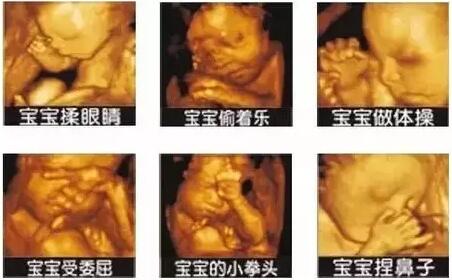

四维超声在三维超声的基础上有了实时动态的效果,准爸爸、准妈妈可以通过屏幕亲眼目睹宝宝在妈妈肚子里运动、呼吸、吞咽、打哈欠、伸舌头等生理活动,非常直观。